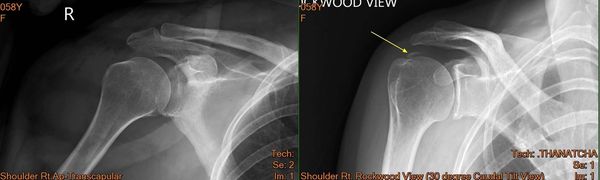

เป็นอาการไหล่ติดเนื่องจาก หินปูน ที่เอ็นกล้ามเนื้อหัวไหล่ ร่วมกับเอ็นหัวไหล่อักเสบ และมีการเยื่อหุ้มหัวไหล่ติดตึงครับ (Calcific Tendinitis)

โดยเคสนี้ช่วงแรกส่งมาทำกายภาพ เพื่อเพิ่มองศาการเคลื่อนไหวหัวไหล่ และลดปวด ซึ่งการรักษาทางกายภาพบำบัดเป็นไปได้ยากมาก ไม่ว่าจะลองทำ Shockwave Laser Ultrasound และ ดัดข้อต่อ (Mobilization) ไม่สามารถลดปวดและเพิ่มองศาการเคลื่อนไหวได้เลย

จึงส่งกลับไปปรึกษาแพทย์เพิ่มเติม โดยแพทย์ก็แนะนำให้ทำการผ่าตัด เพื่อนำหินปูนออก (Calcification Remove) หลังจาการผ่าตัดก็ส่งทำกายภาพต่อ ซึ่งส่งผลค่อนข้างดี สามารถลดปวดและเพิ่มองศาการเคลื่อนไหวได้ง่ายขึ้น ซึ่งเคสนนี้ใช้เวลารักษารวมค่อนข้างนาน โดยรวมใช้เวลาประมาณ เกือบ 1ปี ซึ่งปัจจุบันคนไข้สามารถกลับมาใช้หัวไหล่ได้เกือบปกติ ไม่มีอาการปวด แต่ยังขาดความแข็งแรงของกล้ามเนื้อสะบัก และหัวไหล่อยู่ จึงนัดทำกายภาพบำบัดสัปดาห์ละ1ครั้ง เพื่อปรับเปลี่ยน โปรแกรมออกกำลังกายและลดอาการติดๆจากการใช้งาน